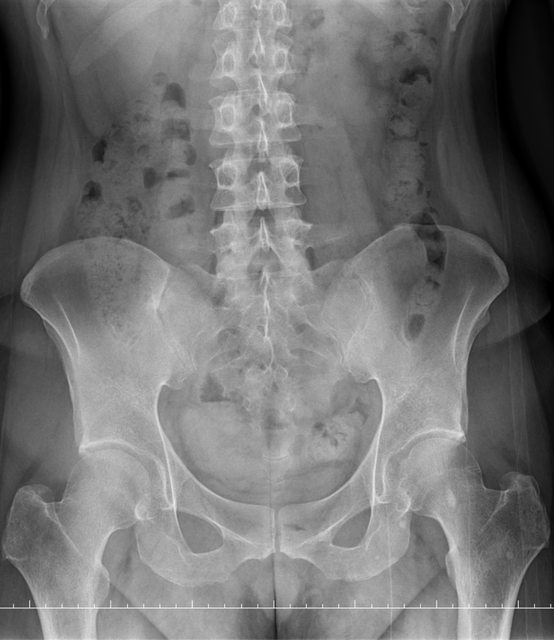

https://i.imgur.com/9HfkOHc.png

骨盆 https://i.imgur.com/h7KknkX.png

股骨頭放大特寫...左邊是右股骨 你覺得哪邊比較正常? https://i.imgur.com/16erxqZ.png

https://i.imgur.com/7NtJDKg.png

https://i.imgur.com/R4JFreK.jpg

醫生似乎很急 就問了二個問題就叫我去照X光 可能就一分鐘吧 回來看了下X光就說可能有神經壓迫 又是14天的消炎止痛藥 說還會痛再來回診或去看脊柱專科或復健科 感覺就是浪費了一天的時間排隊再排隊 沒得到答案 也沒有得到解決... 然後拿了吃越多可能洗腎越快的止痛藥 會不會下次脊柱專科也開14天消炎止痛說如果還有問題叫你去掛神經科? 為何不給我照MRI呢?我第一次去看問了MRI就還是只給我照X光 1.2期X光照了也不一定有異常,我實在不懂不用MRI的邏輯 體驗實在太差了,當然我也知道當有一百號排隊時問診就不可能細到哪怕只有15分 我想不等直接掛看看禮拜三神經科會怎解釋了 ※ 編輯: capybaradash (118.166.44.25 臺灣), 07/31/2023 14:29:17 ※ 編輯: capybaradash (118.166.44.25 臺灣), 07/31/2023 14:37:27

看了下治療方法,那有看等於沒看了 照MRI似乎也是白做,自費照根本浪費 其實X光以我外行人放大好幾倍看過去,左股骨跟大腿骨明顯狀態較差 不清楚醫生是不是有鷹眼,小小一張看過去就說沒什問題 我是不會去考慮手術的 小時候骨折都是看國術館 還減壓股頭打孔...開刀100%NO 治療方法 1.拐杖 2.藥物治療(1)非類固醇類消炎止痛藥(NSAID) (2)口服雙磷酸鹽類藥物 (3)血管擴張劑 (4)高壓氧 目前股骨頭缺血性壞死的治療,根據現有的證據,仍然以手術為主流。 於早期(第一、二期),尚未塌陷的股骨頭缺血性壞死,髖關節減壓手術值得一試, 至於第三、甚至第四期股骨頭缺血性壞死,人工髖關節置換術能夠有效的解除疼痛以及恢 復行走負重的功能。 ※ 編輯: capybaradash (118.166.44.25 臺灣), 07/31/2023 16:04:20

g17321732: 1.骨頭看起來沒大問題,x光不是放大找不一樣這麼簡單 07/31 18:18

g17321732: 3.MRI對你的幫助不大,X光已經足夠清楚,不用花冤枉錢 07/31 18:18

UCCUplz: 哪裡看起來壞死? 07/31 19:52

yasmine1030: 人體不是百分百對稱我實在看不出你X光兩邊股骨有何差 08/01 01:29

yasmine1030: 異 08/01 01:29